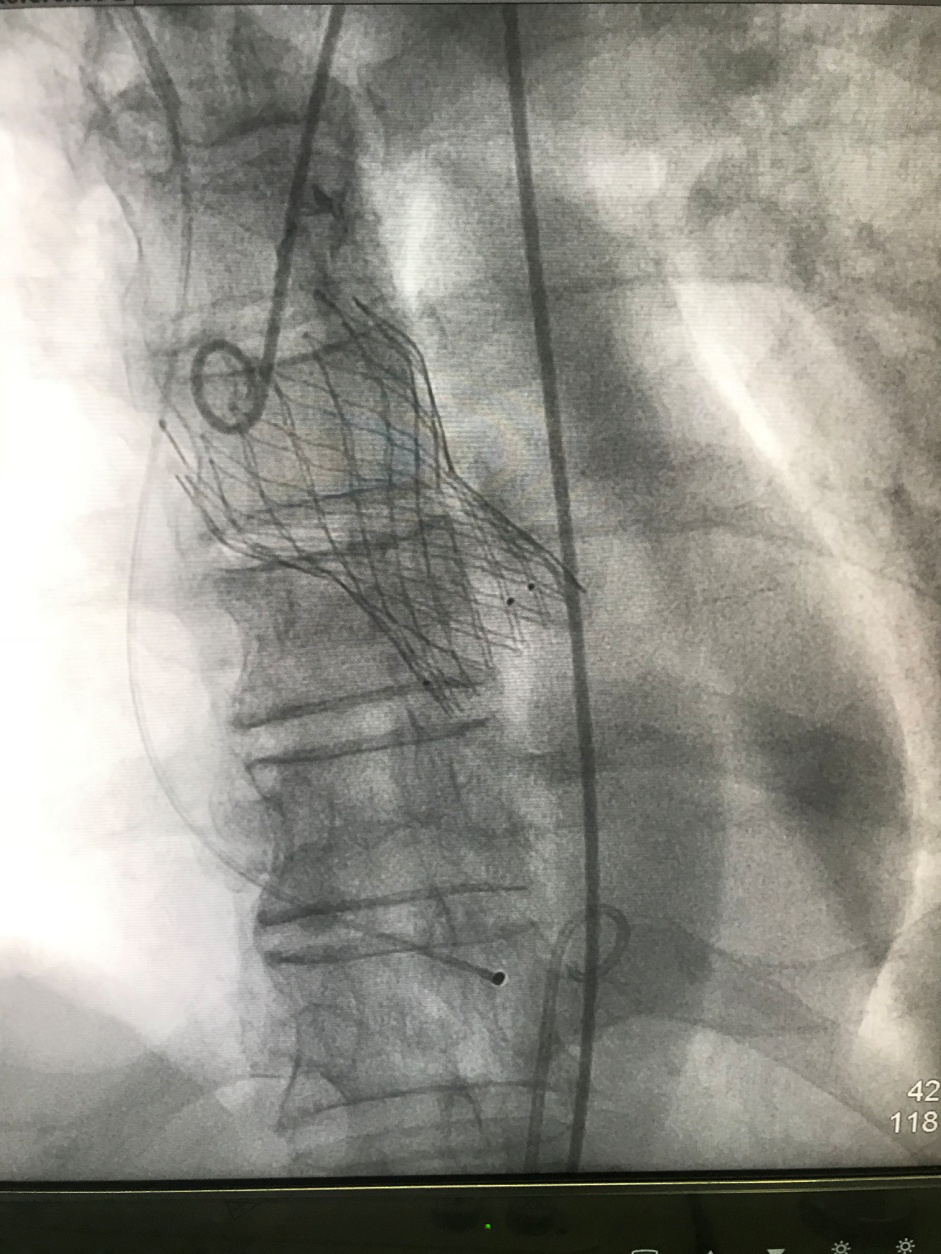

瓣膜成功置入